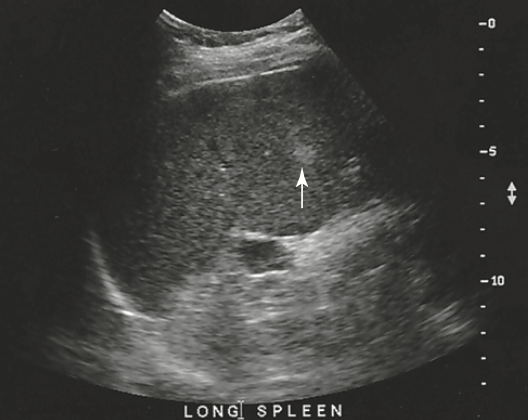

a patient presents with history of alcohol abuse. Which splenic pathology is most likely identified here

splenomegaly